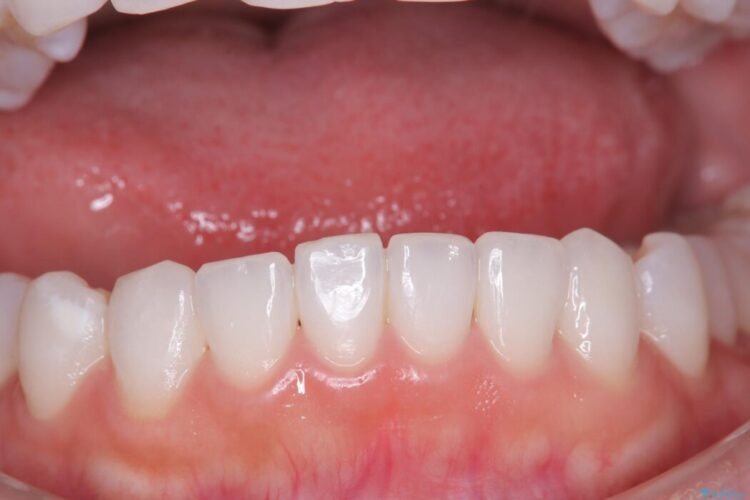

長期的な安定性を重視したセラミック治療

歯と歯の間に虫歯があった患者様です。

治療期間(治療回数):1ヶ月(2~5回) | 概算治療費:13.2万円(税込)(仮歯:10,000円+オールセラミッククラウン 3年保証110,000円)